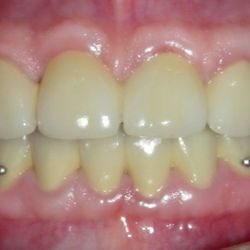

Ο 35χρονος αυτός ασθενής προσήλθε στο ιατρείο παραπονούμενος για το χρώμα και το σχήμα των άνω προσθίων δοντιών του καθώς και για το χρώμα των κάτω προσθίων δοντιών του.

Μετά από ένα βαθύ καθαρισμό των δοντιών, αποφασίστηκε να αποκατασταθούν τα άνω δόντια με νέες ολοκεραμικές όψεις και γέφυρες για σωστή απόδοση χρώματος και σχήματος.

Το χρώμα των κάτω δοντιών βελτιώθηκε μετά απο 3 συνεδρίες λεύκανσης στο ιατρείο.